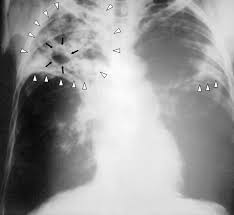

Светски дан туберкулозе

Обележава се